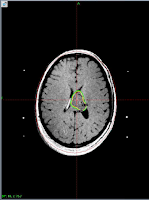

Cavernous sinus hemangioma, total resolution at 6 months.

Twenty five year old lady with restricted Rt.eye movements towards nasal side,

Drooping of rt. eyelid and mid dilated pupil.

MRI showed 2.7+2.9+3.4 cm homogenously enhancing solid mass just above

rt. Cavernous sinus in right side of supra sellar cistern abutting anteromedial

Surface of rt. Temporal lobe, undersurface of thalamus and anterior portion of

right temporal lobe, undersurface of thalamus and anterior portion of rt. half of

midbrain, encasing more than 70% of circumference of top of basilar artery,

causing mild mass effect on pituitary stalk and optic chiasm on rt. Side.

6 month post GKRS

12 Gy at 50 % isodose line.

No Ptosis

Still has devation of rt. eyeball.